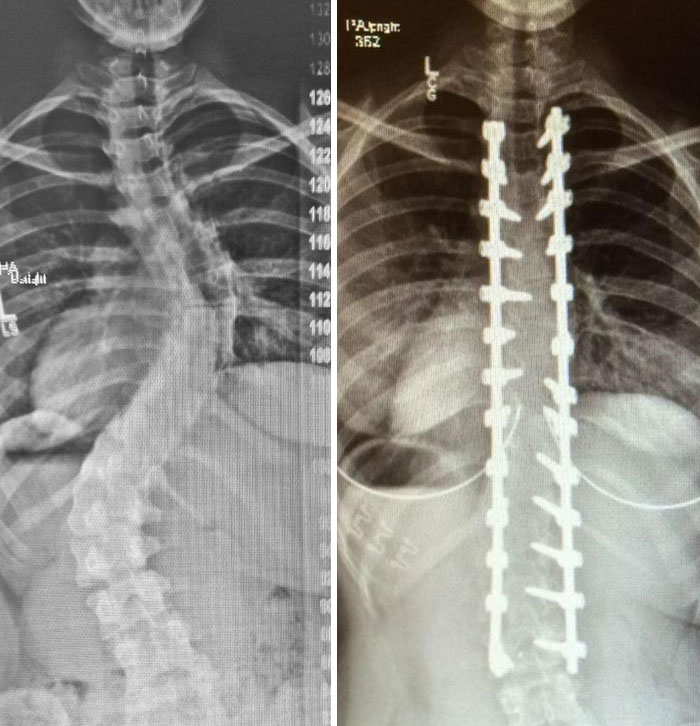

X-Rays Before And After Spinal Fusion Surgery For Scoliosis. I Had Surgery At 12 After The Curvature Continued Getting Worse Despite Interventions Being Taken

15 years since surgery and I have no back-related issues. The only issues are caused by the scar tissue from the auto-bone graft from my hip

6 Years Ago Today I Had A Surgery To Straighten Up My Spine, This Is The Before And After Result. I Gained 5 Cm With The Process

X-Rays Of My Spinal Fusion Surgery Before And After